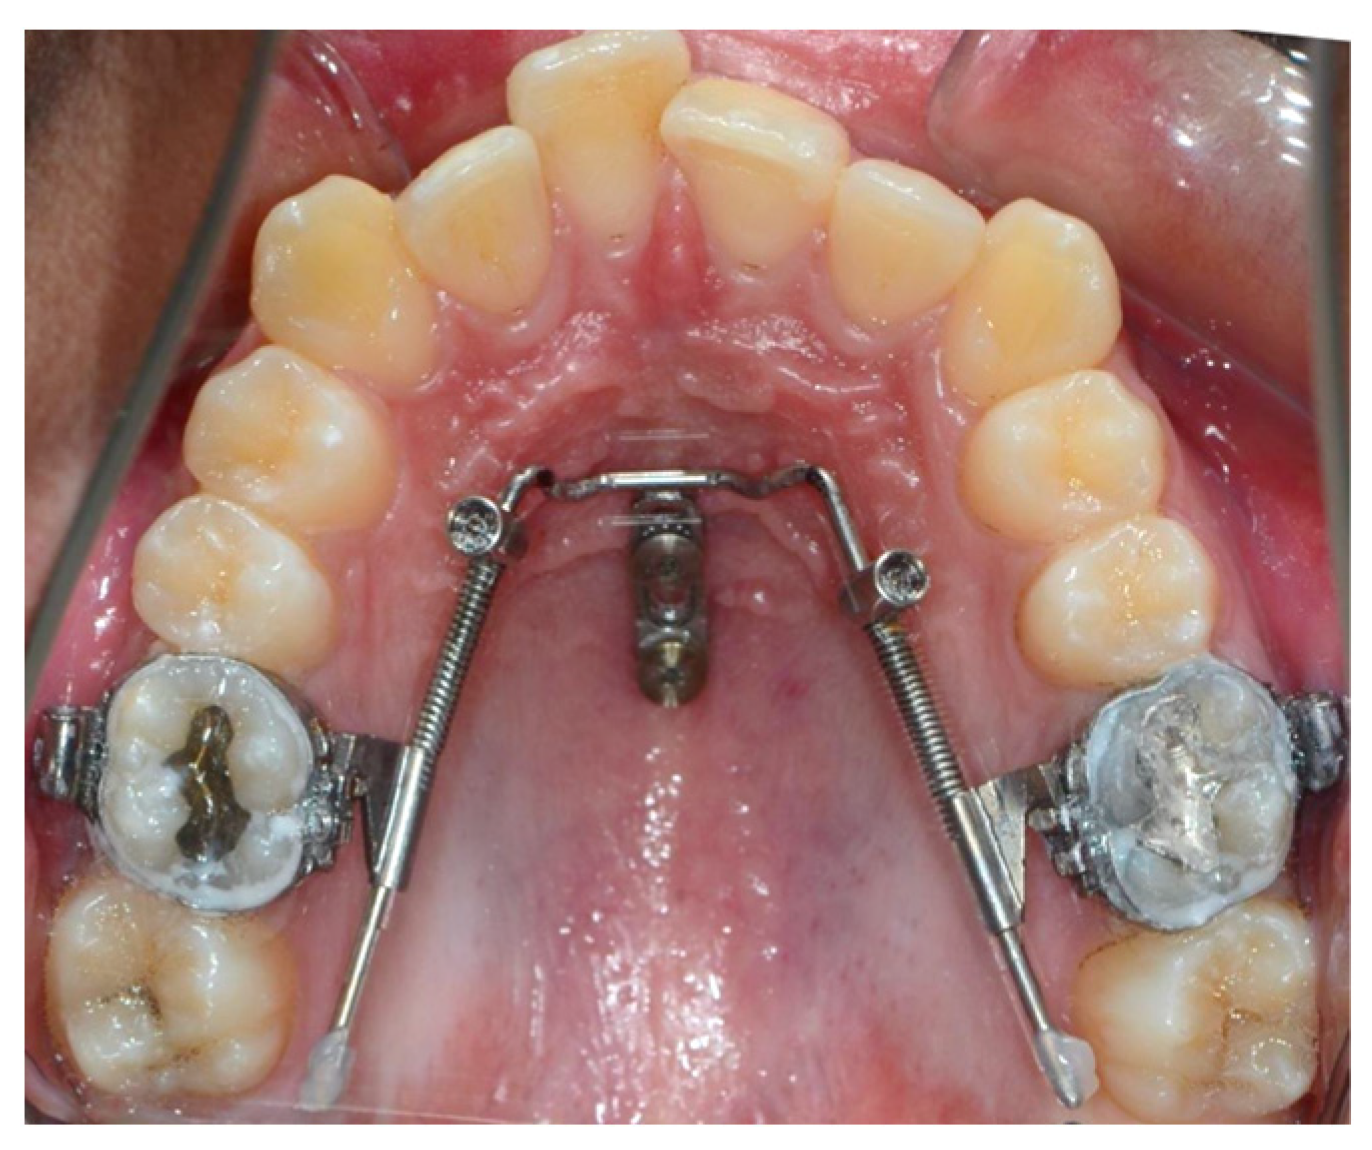

Beneslider Appliance

Miniscrew-Assisted Frog Appliance

Modified Distal Jet Appliance

| Shah et al. (2016) [70] | Skeletal supported (palatinal) | Miniscrew-assisted Frog appliance | 3 mm distal movement of first molars | 200 g | 5 months | No anchorage loss | The Frog appliance is an effective, noninvasive, and compliance-free intraoral distalization appliance for achieving maxillary molar distalization. |